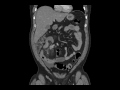

Carcinoid tumor in mesentery with desmoplastic reaction

MR and CT images demonstrate a mass in the right lower quadrant mesentery with adjacent desmoplastic reaction, classic for a mesenteric metastasis from carcinoid.